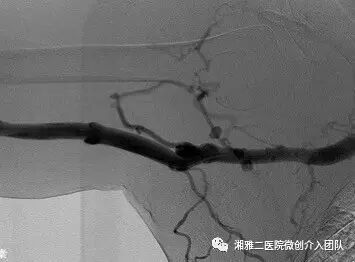

这是该瘘的血管造影表现